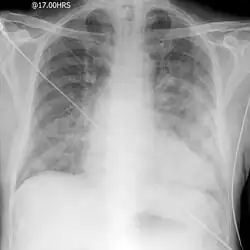

Negative-pressure pulmonary edema

Negative-pressure pulmonary edema (NPPE), also known as Postobstructive Pulmonary Edema, is a clinical phenomenon that results from the generation of large negative pressures in the airways during attempted inspiration against some form of obstruction of the upper airways.[1][2][3] The most common reported cause of NPPE reported in adults is laryngospasm, while the most implicated causes in children are infectious croup and epiglottitis. The large negative pressures created in the airways by inhalation against an upper airway obstruction can lead to fluid being drawn from blood vessels supplying the lungs into the alveoli, causing pulmonary edema and impaired ability for oxygen exchange (hypoxemia).[4] The main treatment for NPPE is supportive care in an intensive care unit and can be fatal without intervention.[1][2]